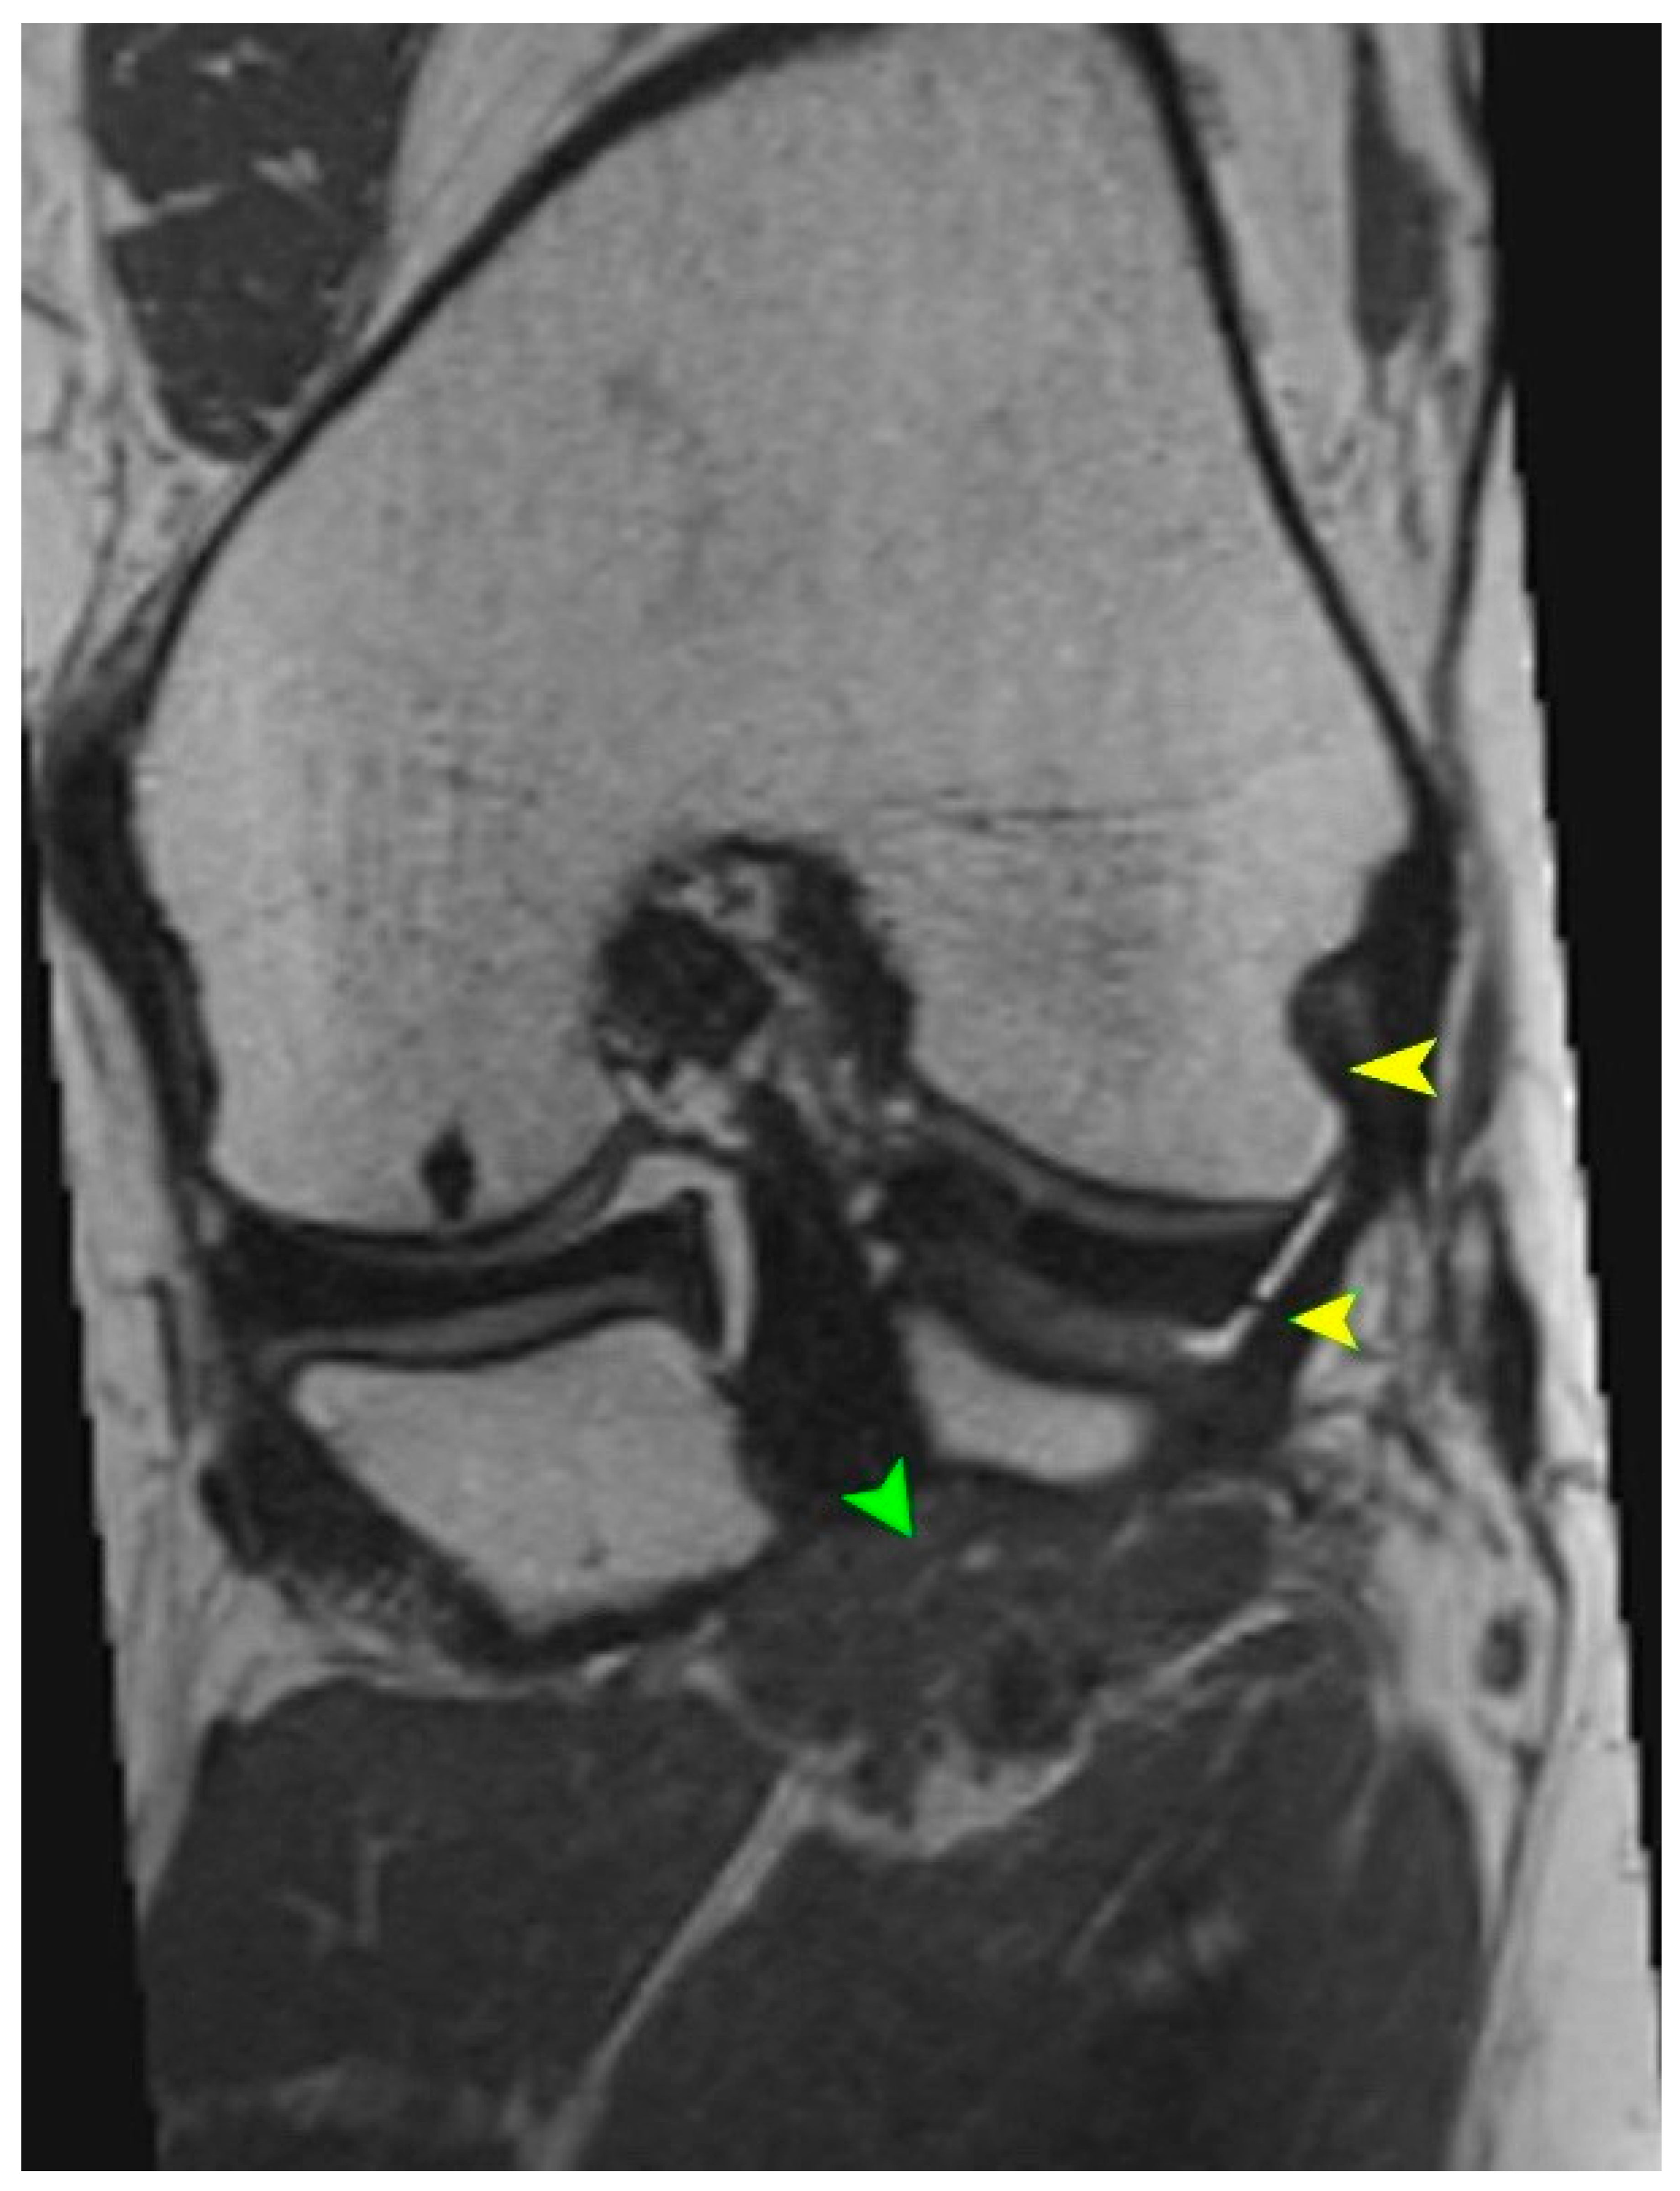

MRI is the gold standard for evaluating soft tissue structures in the knee, including the PT. Optimal visualization of the tendon is achieved using T1 and T2 weighted sequences (Figure 1 and Figure 2) with fat saturation in axial, coronal, and sagittal planes. The PT appears as a low signal intensity structure running obliquely from the lateral femoral condyle to the posteromedial tibia [1,15].

Figure 2.

(a) Axial T1-weighted MRI showing the muscle belly of the popliteus muscle (green arrowhead). (b) Coronal T2-weighted MRI illustrating the tendinous portion of the popliteus (yellow arrowhead). Both panels demonstrate anatomical relationships of the popliteus tendon complex relevant for imaging-based identification.

Particular attention must be given to morphological variations. The presence of bifid tendons or accessory bands (Types II–IV according to Olewnik’s classification) can be mistaken for tendon ruptures, scar tissue, or pathological adhesions [11]. Recognition of these variants is essential to avoid misdiagnosis.

In acute traumatic cases, key findings include hyperintensity within the tendon on T2 weighted images, peritendinous fluid, discontinuity of tendon fibers, and surrounding soft tissue edema [1]. MRI can also reveal the secondary signs of PT injury, such as displacement of the lateral meniscus, stretching of the fibular collateral ligament, and abnormal tibial rotation [15]. Studies have shown that awareness and identification of the anatomical variability of the PT during MRI interpretation of acute knee injuries can improve diagnostic sensitivity and specificity by 15–20% [6].